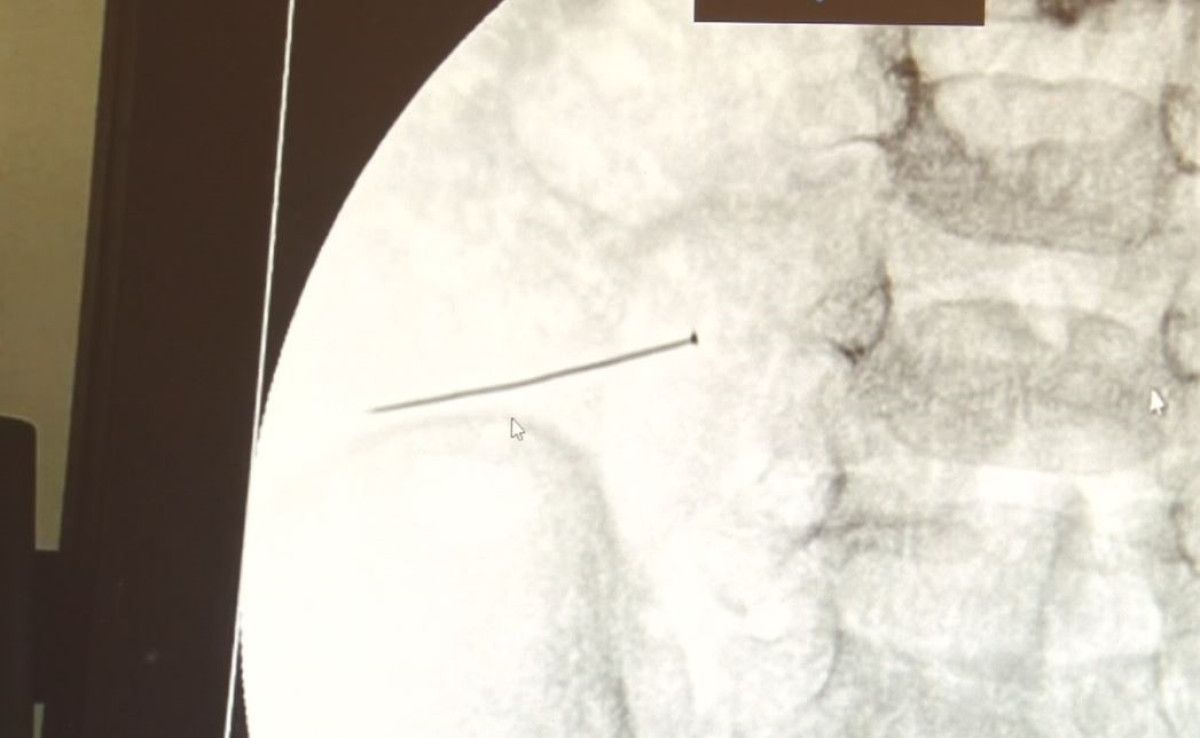

3 SANTİMLİK İĞNE BAĞIRSAĞINI DELDİ

Burada yapılan tetkiklerde 2 yaşındaki çocuğun ince bağırsağında yaklaşık 3 santimlik toplu iğne olduğu ve bağırsağı deldiği belirlendi.

Ertesi gün bağırsakta delinmeyle sonuçlanmış ve çocukta da ciddi semptomlar meydana getirmişti. Bu şekilde hasta bize başvurdu. Tetkikler sonucunda yabancı cismi tespit ettik, semptomları ve bulgularına göre de çocuğu ameliyata aldık. Yaklaşık 3 santim boyunda bir toplu iğnenin ince bağırsağı deldiğini, ince bağırsaktaki içeriğin de karın içerisine dolduğunu gördük. Ameliyatı başarılı bir şekilde tamamladık, yaklaşık 1 saat süren bir ameliyattı” dedi.

Öte yandan, yaklaşık 3 santimlik toplu iğne filme yansıyan görüntüsüyle gözler önüne serildi.